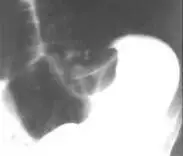

乙状结肠扭转